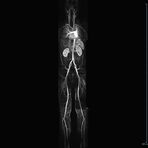

- Bauchgefäße

- Erfassung und Verlaufskontrolle bei arteriellen Aneurysmen (Aussackungen der Arterien), vor allem der Bauchaorta

- Darstellung von Gefäßengen an Nierenarterien, Baucharterien und Becken-/Beinarterien

- MR-Angiographie mit Kontrastmittel

- Erfassung arterieller und venöser Gefäße/Bypässe aller Körperregionen mit 3D-Rekonstruktion

- je nach klinischer Fragestellung zeitaufgelöste MR-Angiographie (4D-MRA) z.B. bei Frage arteriovenöse Fistel/ Shunt oder Darstellung Unterschenkelarterien vor geplanter Bypassoperation.